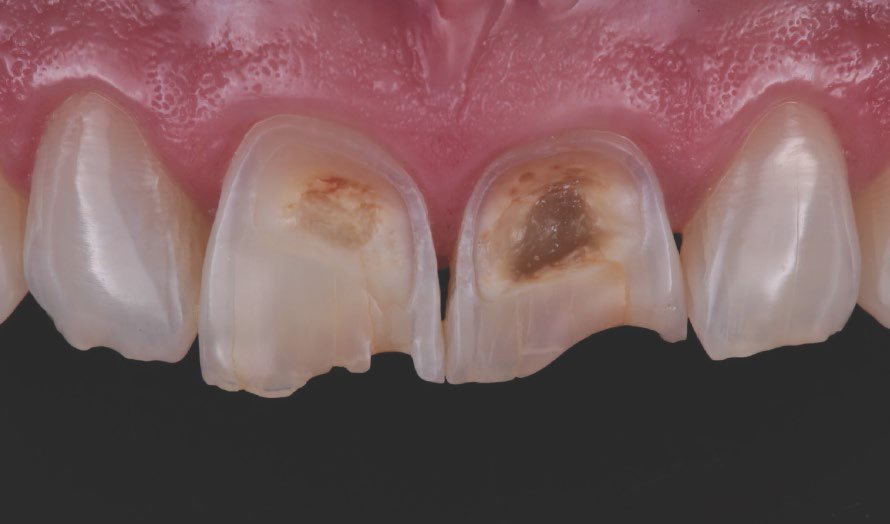

Patient had deep erosive lesions affecting vestibular aspects of maxillary central incisors. The challenge was to improve esthetics and protect the remaining tooth structure.

Preoperative frontal view of the patient’s teeth, showing severe erosive tooth wear on the vestibular surfaces and incisal edges.

Detailed view of the maxillary incisors. The teeth didn’t show any highly translucent areas, so the use of a single shade/opacity of 3M™ Filtek™ Universal Restorative was selected.

Lateral view of the anterior teeth revealed the depth of the lesions on the vestibular surfaces.